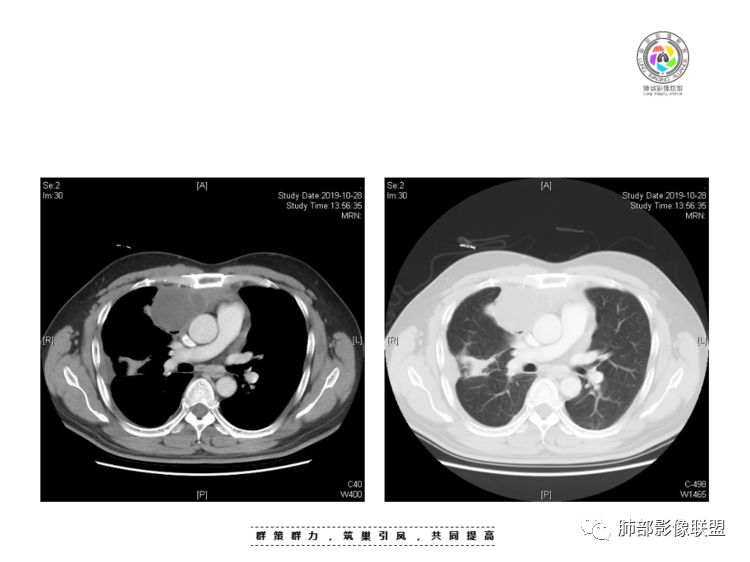

南边:我总觉得这个纵隔内不像是一个肿块的改变,扁平,周围蔓延:有符合炎性的的特点,或者肿瘤的侵犯;但是肿瘤的侵犯,不大符合,实性部位的边缘过于柔和,没有毛糙的侵犯边缘。

肺内结节,近端支气管堵塞狭窄

整体边缘收缩,部分膨隆

炎性要考虑,但恶性不能排除

2、前纵隔内病灶囊实性混杂密度病灶,囊性病灶主要位于右侧,张力较高,有分隔影,囊壁右侧缘光整,病灶左侧实性部分边界不清明显强化,病灶肺瘤交界面大部分边界清楚,部分模糊。

纵隔内病灶不符合肺癌转移途径,且纵隔内单发的囊实性转移罕见。淋巴瘤无论是分布、形态、密度、还是强化方式度不符合。

患者缺乏纵隔炎的临床表现,囊性病损更难以解释。

胸腺瘤/胸腺癌符合吗?

胸腺瘤/胸腺癌:病灶内那么大的囊,常规考虑B型以上胸腺瘤,囊内有分隔影,病灶周围脂肪间隙模糊,常规考虑侵袭性胸腺瘤或胸腺癌,若侵袭性胸腺瘤,常侵犯胸膜、心包,很少累及肺。胸腺癌易侵犯胸膜、肺并纵隔淋巴结及远处转移。但肺内腺癌形态更符合原发灶。胸膜及叶间裂转移则即可来自肺,也可来自胸腺癌。